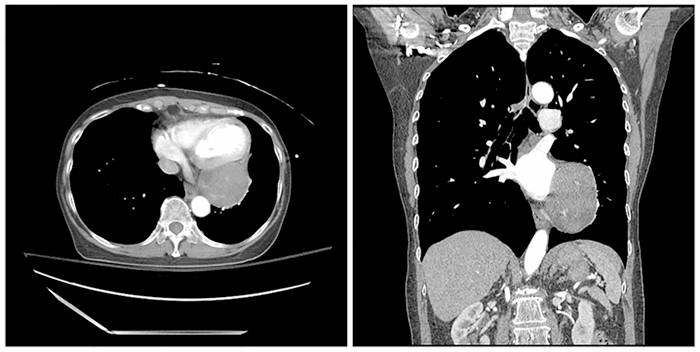

A 70-year-old female without significant co-morbidities presented to the emergency room after being involved as a restrained passenger in a high-speed motor vehicle crash. Because of the high-energy mechanism and complaints of anterior chest pain, the patient underwent CT of the chest. In addition to a minimally displaced fracture of the upper sternal body, imaging identified a 4.7 cm × 5.9 cm × 8.1 cm soft tissue mass adjacent to the left atrioventricular groove and circumflex coronary artery (Figure 1).

Figure 1. Axial and Coronal Cuts of a Thoracic CT Scan with Trauma-Protocol IV Contrast Demonstrate a Heterogeneous Left-Sided Mediastinal Tumor with Unclear Anatomical Association. Published with Permission

There were no suggestions that this incidental lesion was associated with the traumatic event. The patient was discharged from the hospital the following day, and an outpatient workup of the cardiac mass was recommended. The patient underwent a transthoracic echocardiogram demonstrating normal biventricular function and no valvular dysfunction, followed by a gated cardiac MRI and PET-CT (Figure 2).

Figure 2. Axial T1 Double IR. Published with Permission

A) +C T1 Double IR; B) T2 Double IR FS; C) Cuts of a thoracic MRI demonstrating heterogeneous nature of mediastinal mass as well as its close association with left atrioventricular groove

This additional imaging showed a large mass in the posterolateral AV groove inseparable from the myocardium, immediately inferior to the atrial appendage with associated distortion of the left inferior pulmonary vein. The mass was heterogeneous on T2 weighted post-gadolinium imaging and on PET and was therefore considered suspicious for sarcoma. The PET was otherwise negative for regional or distant disease. A CT-guided core needle biopsy was acellular and demonstrated only densely packed fibrin.